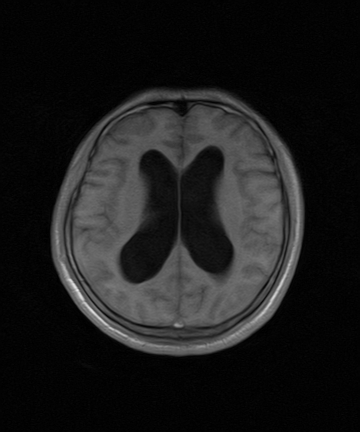

标题: MRI2064:少见病例。男性52,视力下降多年。 [打印本页]

标题: MRI2064:少见病例。男性52,视力下降多年。

四脑室区见混杂信号占位影,脑室系统扩张明显,临近结构显著受压称位,患者52岁,多考虑室管膜瘤可能性大

考虑第四脑室室管膜瘤并阻塞性脑积水。

考虑第四脑室室管膜瘤并梗阻性脑积水;部分性空蝶鞍;左侧上颌窦粘膜下囊肿。

考虑第四脑室室管膜瘤【血供丰富血管母细胞瘤可能】并梗阻性脑积水;部分性空蝶鞍;左侧上颌窦粘膜下囊肿。

比较典型的脉络丛乳头状瘤并脑积水,鉴别小脑蚓部血管母细胞瘤。